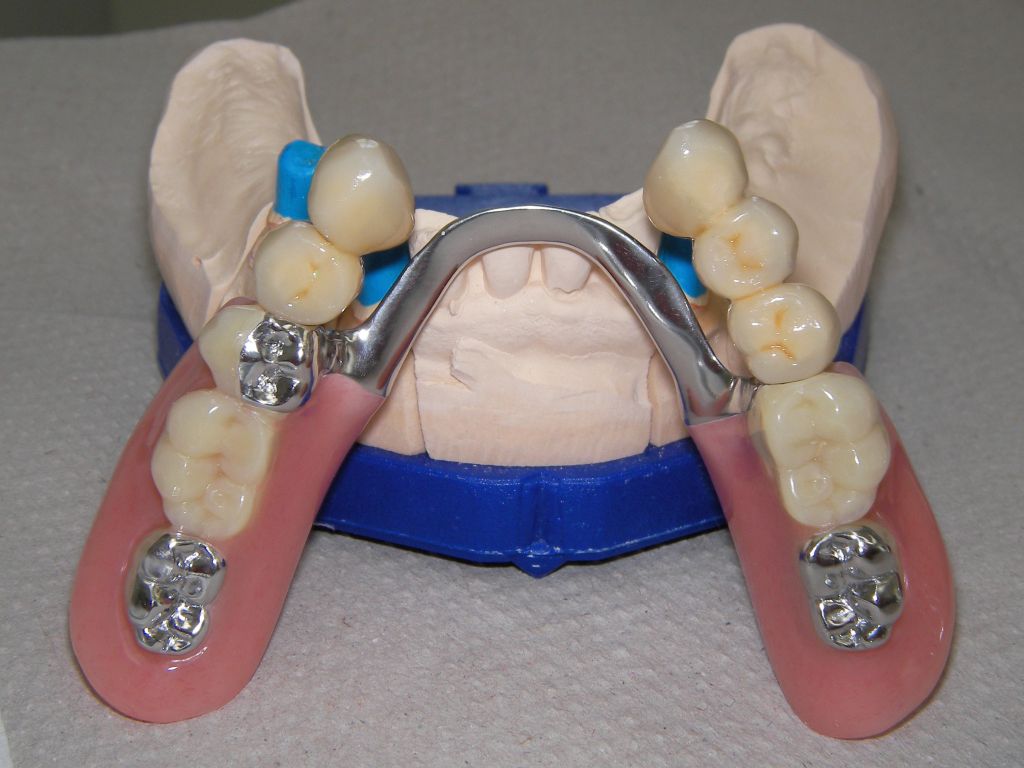

Links das Bild zeigt das Metallgerüst, das später mit Keramik verblendet wurde. Um eine einfache Mundhygiene ebenso wie eine hohe zahntechnische Präzsion zu erreichen, wurden risikobehaftete Verblockungen minimiert. Rechts die Ästhetikeinprobe bei entspannter Oberlippe.

Oberkiefer von vorne

Unterkiefer von vorne

Links Bilder des Oberkiefers, rechts des Unterkiefers. Die Arbeit wurde von dem Dentallabor "Heitmeyer Zahntechnik", Osnabrück, gefertigt. Dem Labor ist hier für die hervorragende Arbeit zu danken, dem Patienten für die Freigabe der Bilder!

Die Zähne auf der Prothese sind aus verarbeitungstechnischen Gründen auch heute meist noch aus Kunststoff, auch wenn teurere Keramikzähne möglich wären. Kunststoff verschleißt über die Jahre, der Biß verändert sich. Um letzteres zu verhindern, sind hier zusätzlich Metallkauflächen eingearbeitet, die sich nicht verändern werden.